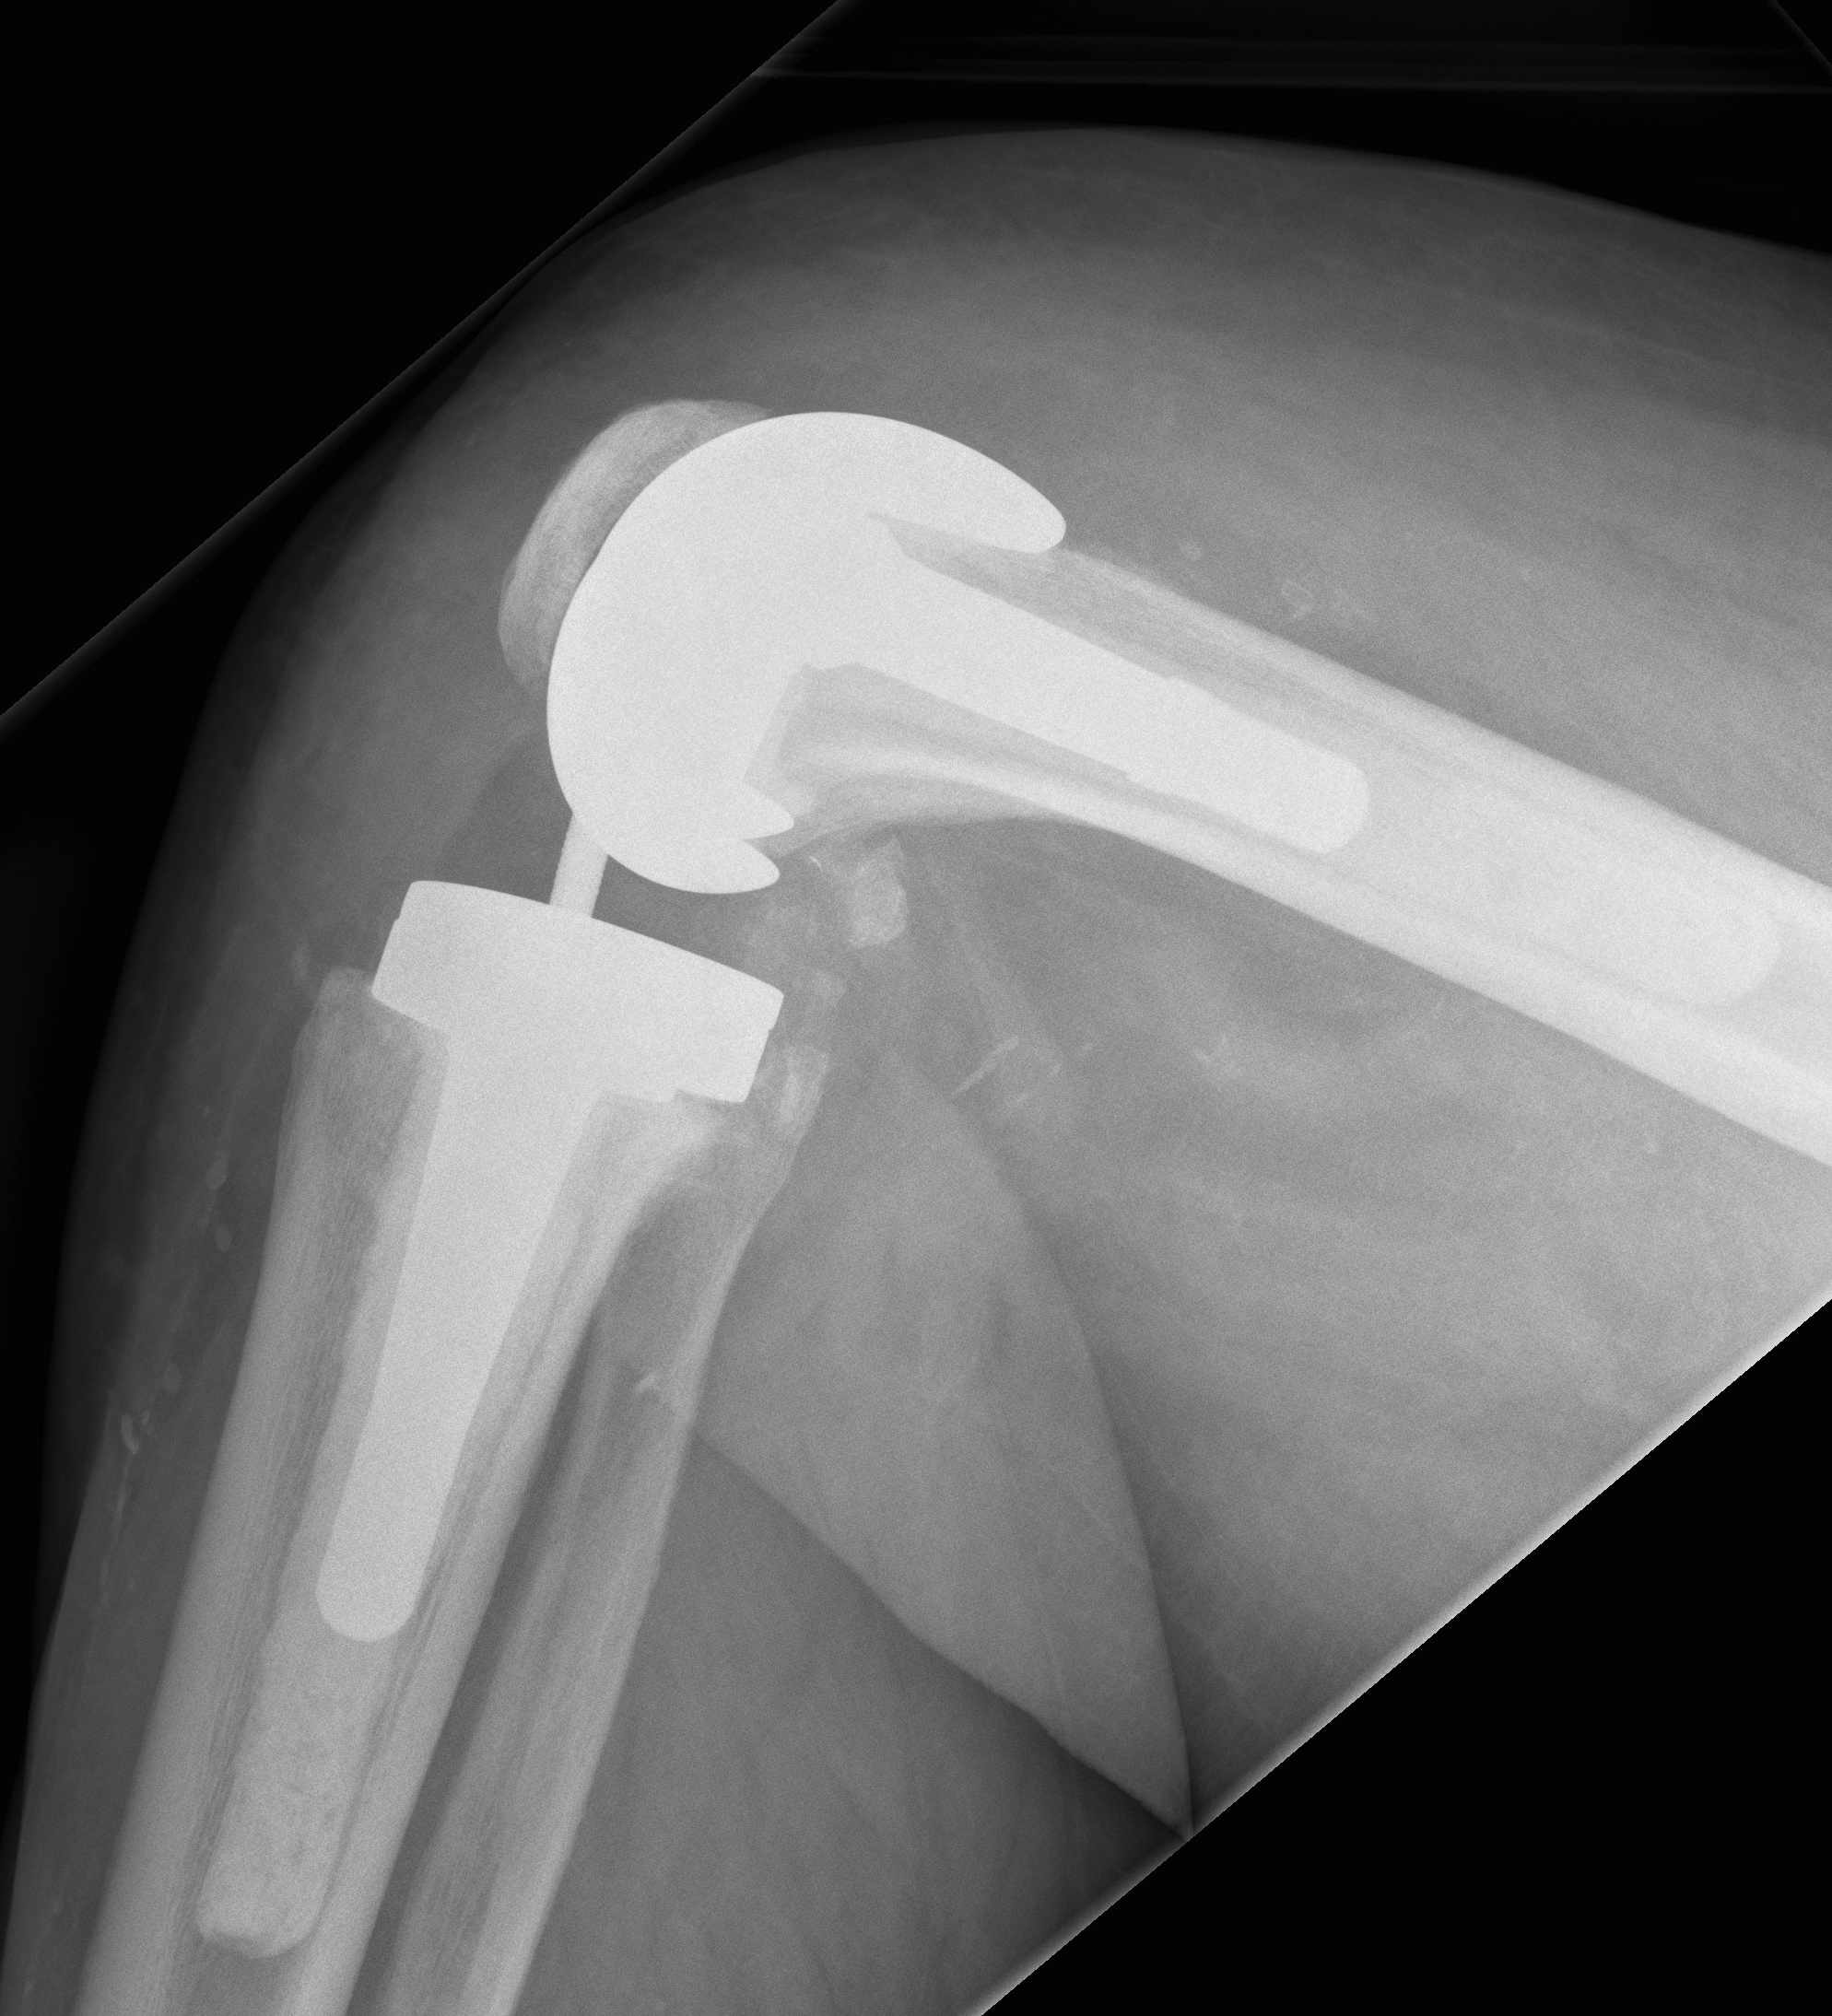

3. Constrained Hinged / Rotating Hinged

Design

1. Uniplanar hinge

- prohibited rotational motion

- high rate of aseptic loosening

- historical

2. Rotating Hinge

- linked with an axle

- restricts varus-valgus and translation

- permit rotation of the tibial bearing about a yoke on the tibial platform

- again need long stems to disperse forces